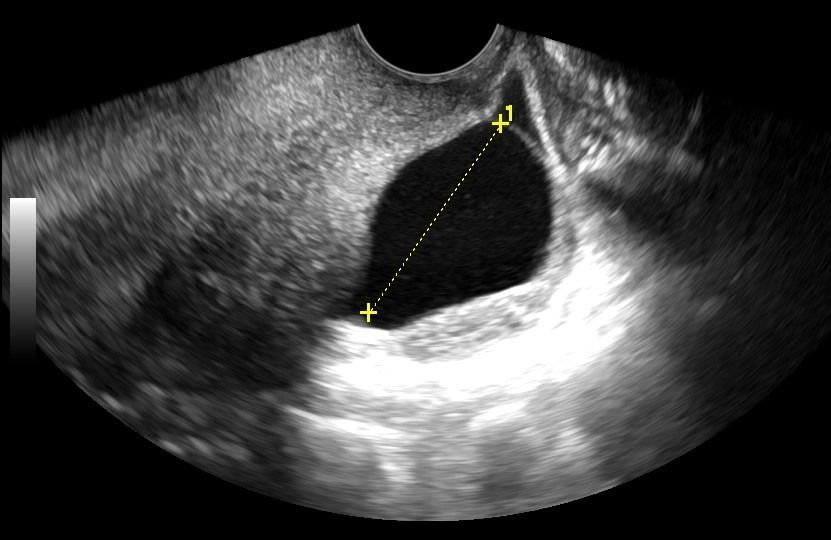

- Μήτρα: Με το Διακολπικό Υπερηχογράφημα, μπορεί να αξιολογηθεί το μυομήτριο και να εντοπιστεί η παρουσία ινομυωμάτων. Το πάχος του ενδομητρίου μπορεί να μετρηθεί με ακρίβεια, κάτι που είναι κρίσιμο τόσο για γυναίκες αναπαραγωγικής ηλικίας όσο και για γυναίκες μετά την εμμηνόπαυση ή μετά από θεραπευτικά σχήματα για νεοπλάσματα.

- Ακρίβεια: Για την ακριβή μέτρηση του πάχους του ενδομητρίου και την αξιολόγηση της ωοθηκικής δομής, το Διακολπικό Υπερηχογράφημα παρέχει σαφέστερα αποτελέσματα σε σχέση με το υπερηχογράφημα κάτω κοιλίας.